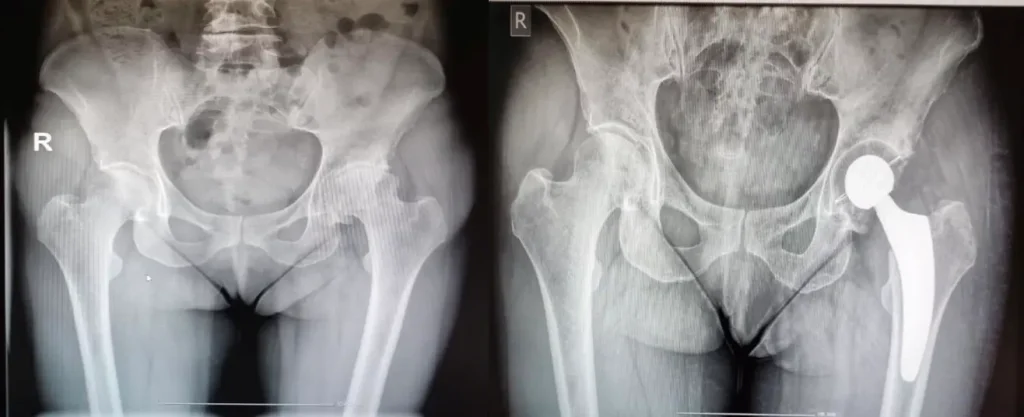

Ολική Αρθροπλαστική Ισχίου

τι Είναι;

Η ολική αρθροπλαστική του ισχίου είναι μία επέμβαση κατά την οποία γίνεται αντικατάσταση των φθαρμένων αρθρικών επιφανειών του ισχίου με τεχνητές προθέσεις. Στόχος της επέμβασης είναι αφενός η ανακούφιση από τον πόνο και αφετέρου η ανάκτηση του πλήρους

εύρους κίνησης της άρθρωσης.